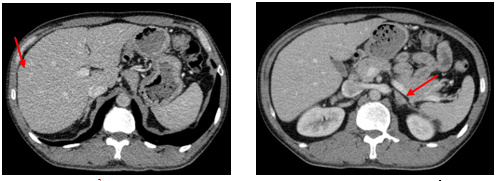

- Chụp cắt lớp vi tính lồng ngực: phim trước điều trị

Hình 1. Trên phim chụp CT lồng ngực ở cửa sổ nhu mô: thùy trên phổi trái có khối đặc tròn bờ tua gai, kích thước: 29 x20mm, kính mờ và dày kẽ xung quanh, lân cận có nốt bán đặc kích thước 29 x 17mm, ngấm thuốc không đồng nhất sau tiêm, nghi ngờ có phần xâm lấn trung thất trước. Nhu mô thùy còn lại và nhu mô phổi phải lan tỏa các nốt đặc tròn to nhỏ không đều, đường kính: 2-8mm.

Hình 2. Cửa sổ trung thất: Vài hạch trung thất cạnh khí, hạch lớn nhất kích thước 14x7mm

- Cắt lớp vi tính lồng ngực:

Sau 3 tháng điều trị đích:

- U nguyên phát và u thứ phát ở cả 2 phổi đều giảm kích thước rất nhiều, không thấy hạch trung thất.

Sau 6 tháng điều trị:

- U nguyên phát chỉ còn kích thước rất nhỏ, u thứ phát 2 bên phổi đã mất hết.